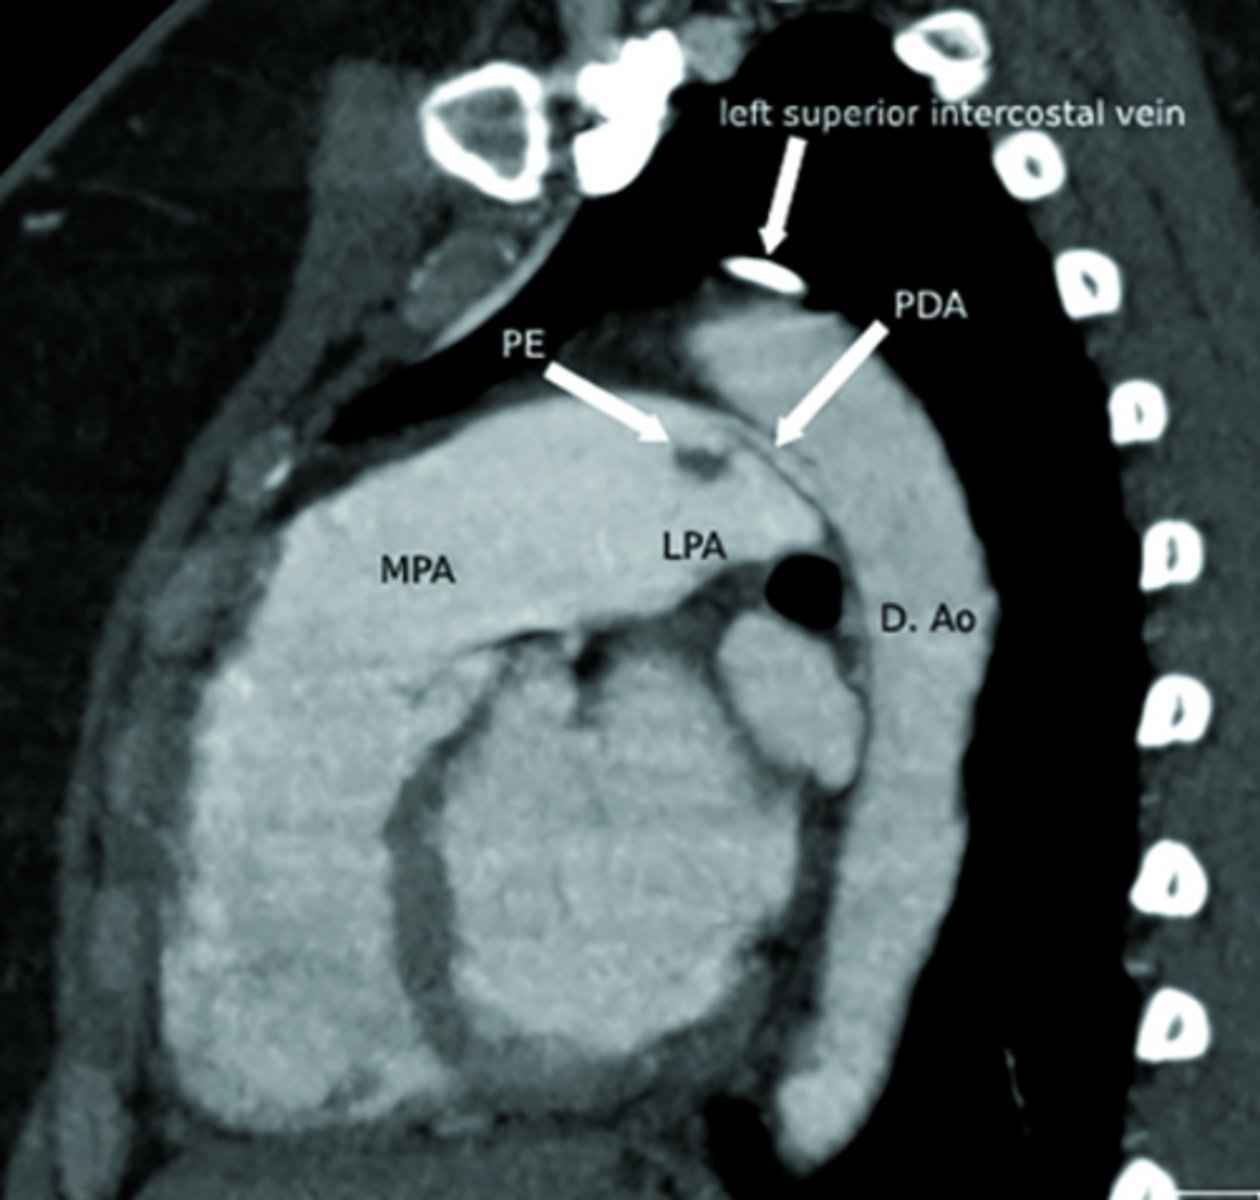

Ductus arteriosus

What is the ductus arteriosus?

A structure in embryo connecting the pulmonary trunk to the aorta.

Acts as a shunt - prevents blood from going back to lungs and instead dumps it back into aorta.

What does a machine-like murmur at the left 2nd intercostal space suggest?

Patent ductus arteriosus

What is patent ductus arteriosus (PDA)?

Persistent connection between the pulmonary artery and aorta after birth.